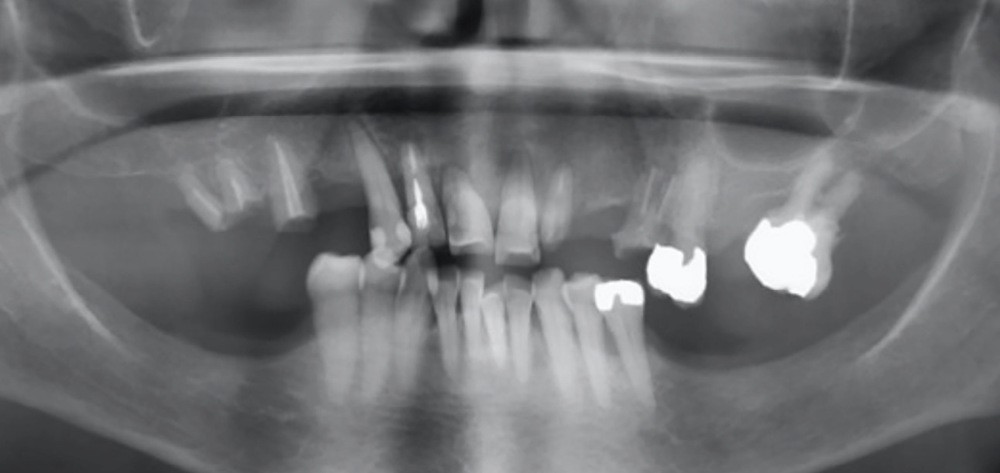

À l’examen endobuccal, le sondage parodontal révèle une parodontite généralisée stade 4 grade A [1] caractérisée par des pertes d’attaches ≥ 5 mm, une alvéolyse au niveau radiographique > 50 % de la hauteur radiculaire, des pertes dentaires en raison de la maladie parodontale et des migrations secondaires dentaires.

Le pronostic dentaire général est mauvais [2], et la conservation des dents résiduelles n’est donc pas retenue (fig. 2).